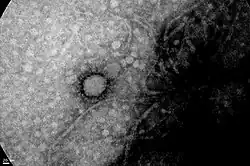

The COVID-19 pandemic in Argentina is part of the worldwide pandemic of coronavirus disease 2019 (COVID-19) caused by severe acute respiratory syndrome coronavirus 2 (SARS-CoV-2). As of 21 August 2025, a total of 10,113,909 people were confirmed to have been infected, and 130,783 people were known to have died because of the virus.[3]

On 12 January, the World Health Organization (WHO) confirmed that a novel coronavirus was the cause of a respiratory illness in a cluster of people in Wuhan City, Hubei Province, China, who was reported to the WHO on 31 December 2019.[20][21] The case fatality rate for COVID-19[22][23] has been much lower than the 2002–2004 SARS outbreak, but transmission has been significantly greater, with a significant total death toll.[24][22] Model-based simulations for Argentina indicate that the 95% confidence interval for the time-varying reproduction number Rt exceeded 1.0 from April to July 2020, after which it diminished to below 1.0 in October and November 2020.[25]